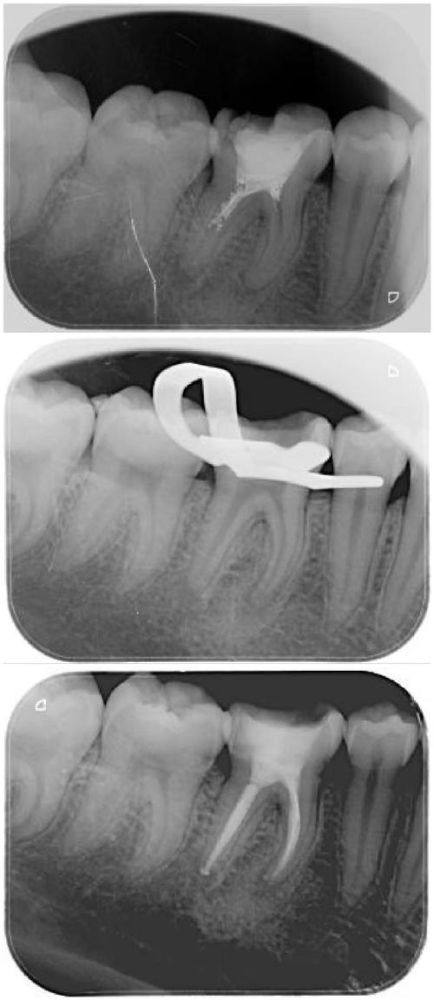

复杂根管治疗:可开展复杂根管再治疗、钙化根管疏通以及热牙胶根管充填术,针对疑难根管问题具备丰富的处理经验,提升根管治疗的成功几率。

依托天津市北辰医院口腔科配备的蔡司根管显微镜、DENSPLY X-SMART镍钛机动根管预备系统、B&L热牙胶充填系统等精良设备,能够更精细化地完成根管诊疗操作,减少患者治疗过程中的不适感,保护诊疗成效。